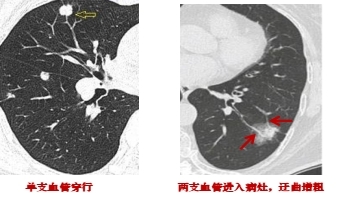

3.結(jié)節(jié)與血管的關(guān)系:如果肺結(jié)節(jié)內(nèi)部有血管匯入,周邊有血管伴行,且血管扭曲、增粗、變細(xì)或被中斷,往往提示惡性。